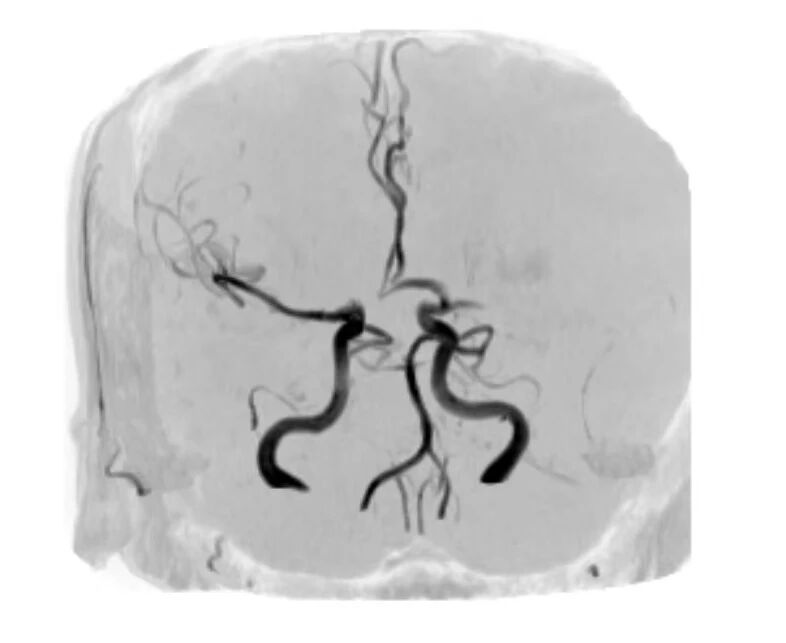

时间就是大脑,救治刻不容缓。赵智强即刻为患者实施静脉溶栓治疗,从患者入院到用药,仅用时10分钟(DNT=10分钟),为救治争取了宝贵时间。后续治疗中,医护团队观察到患者溶栓后言语、肢体功能恢复有限,结合头颅核磁提示左侧大脑中动脉显影不良,果断启动“桥接”救治方案,迅速将患者转运至导管室。但通过动脉造影,发现在短短的时间内(约20分钟),患者左侧大脑中动脉已完全再通,血流灌注恢复良好(mTICI 3级)。在检查过程中,患者右侧肌力逐渐恢复至4级,次日言语及肢体功能基本正常,NIHSS评分降至0分,救治效果显著。